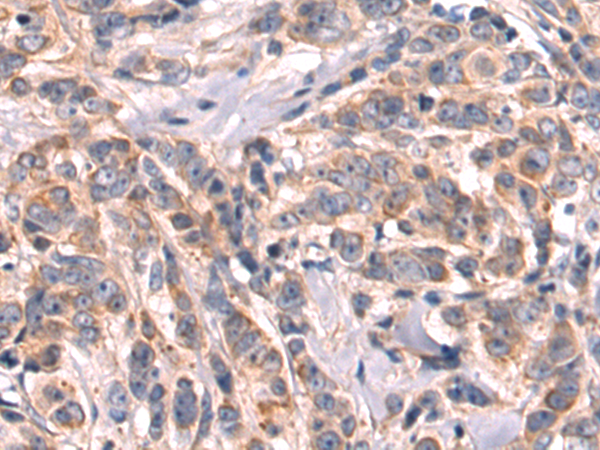

分类: 科研抗体货号: P09413别名:应用: IHC反应种属: Human, Mouse, Rat